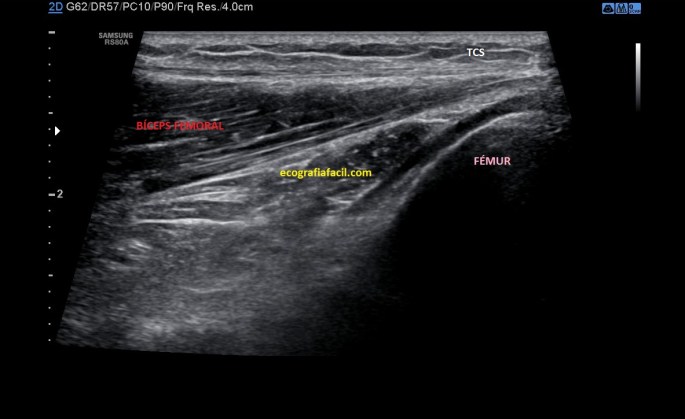

La inserción del Bíceps Femoral es diferente, lo hace, tanto su porción larga, como su porción corta, unidas, en la cabeza del Peroné, por tanto lateral. Mira:

Normalidad

Esta es una imagen, conseguida con un corte longitudinal, en situación normal…mira la misma imagen en una situación de rotura del Tendón del Bíceps Femoral:

En la imagen patológica que ves arriba es vital la localización del Peroné. Ahora te voy a pedir que compares y que observes como en la imagen de normalidad vemos un tendón hiperecogénico, marcado por flechas amarillas, homogéneo insertando en el Peroné…en la imagen siguiente el tendón está aumentado de tamaño, heterogéneo y con componente líquido, lo marcan las líneas rojas…Es precioso, ¿verdad?…ambas imágenes son de deportistas, una corredora y amiga, la imagen de normalidad y un futbolista, la imagen patológica.